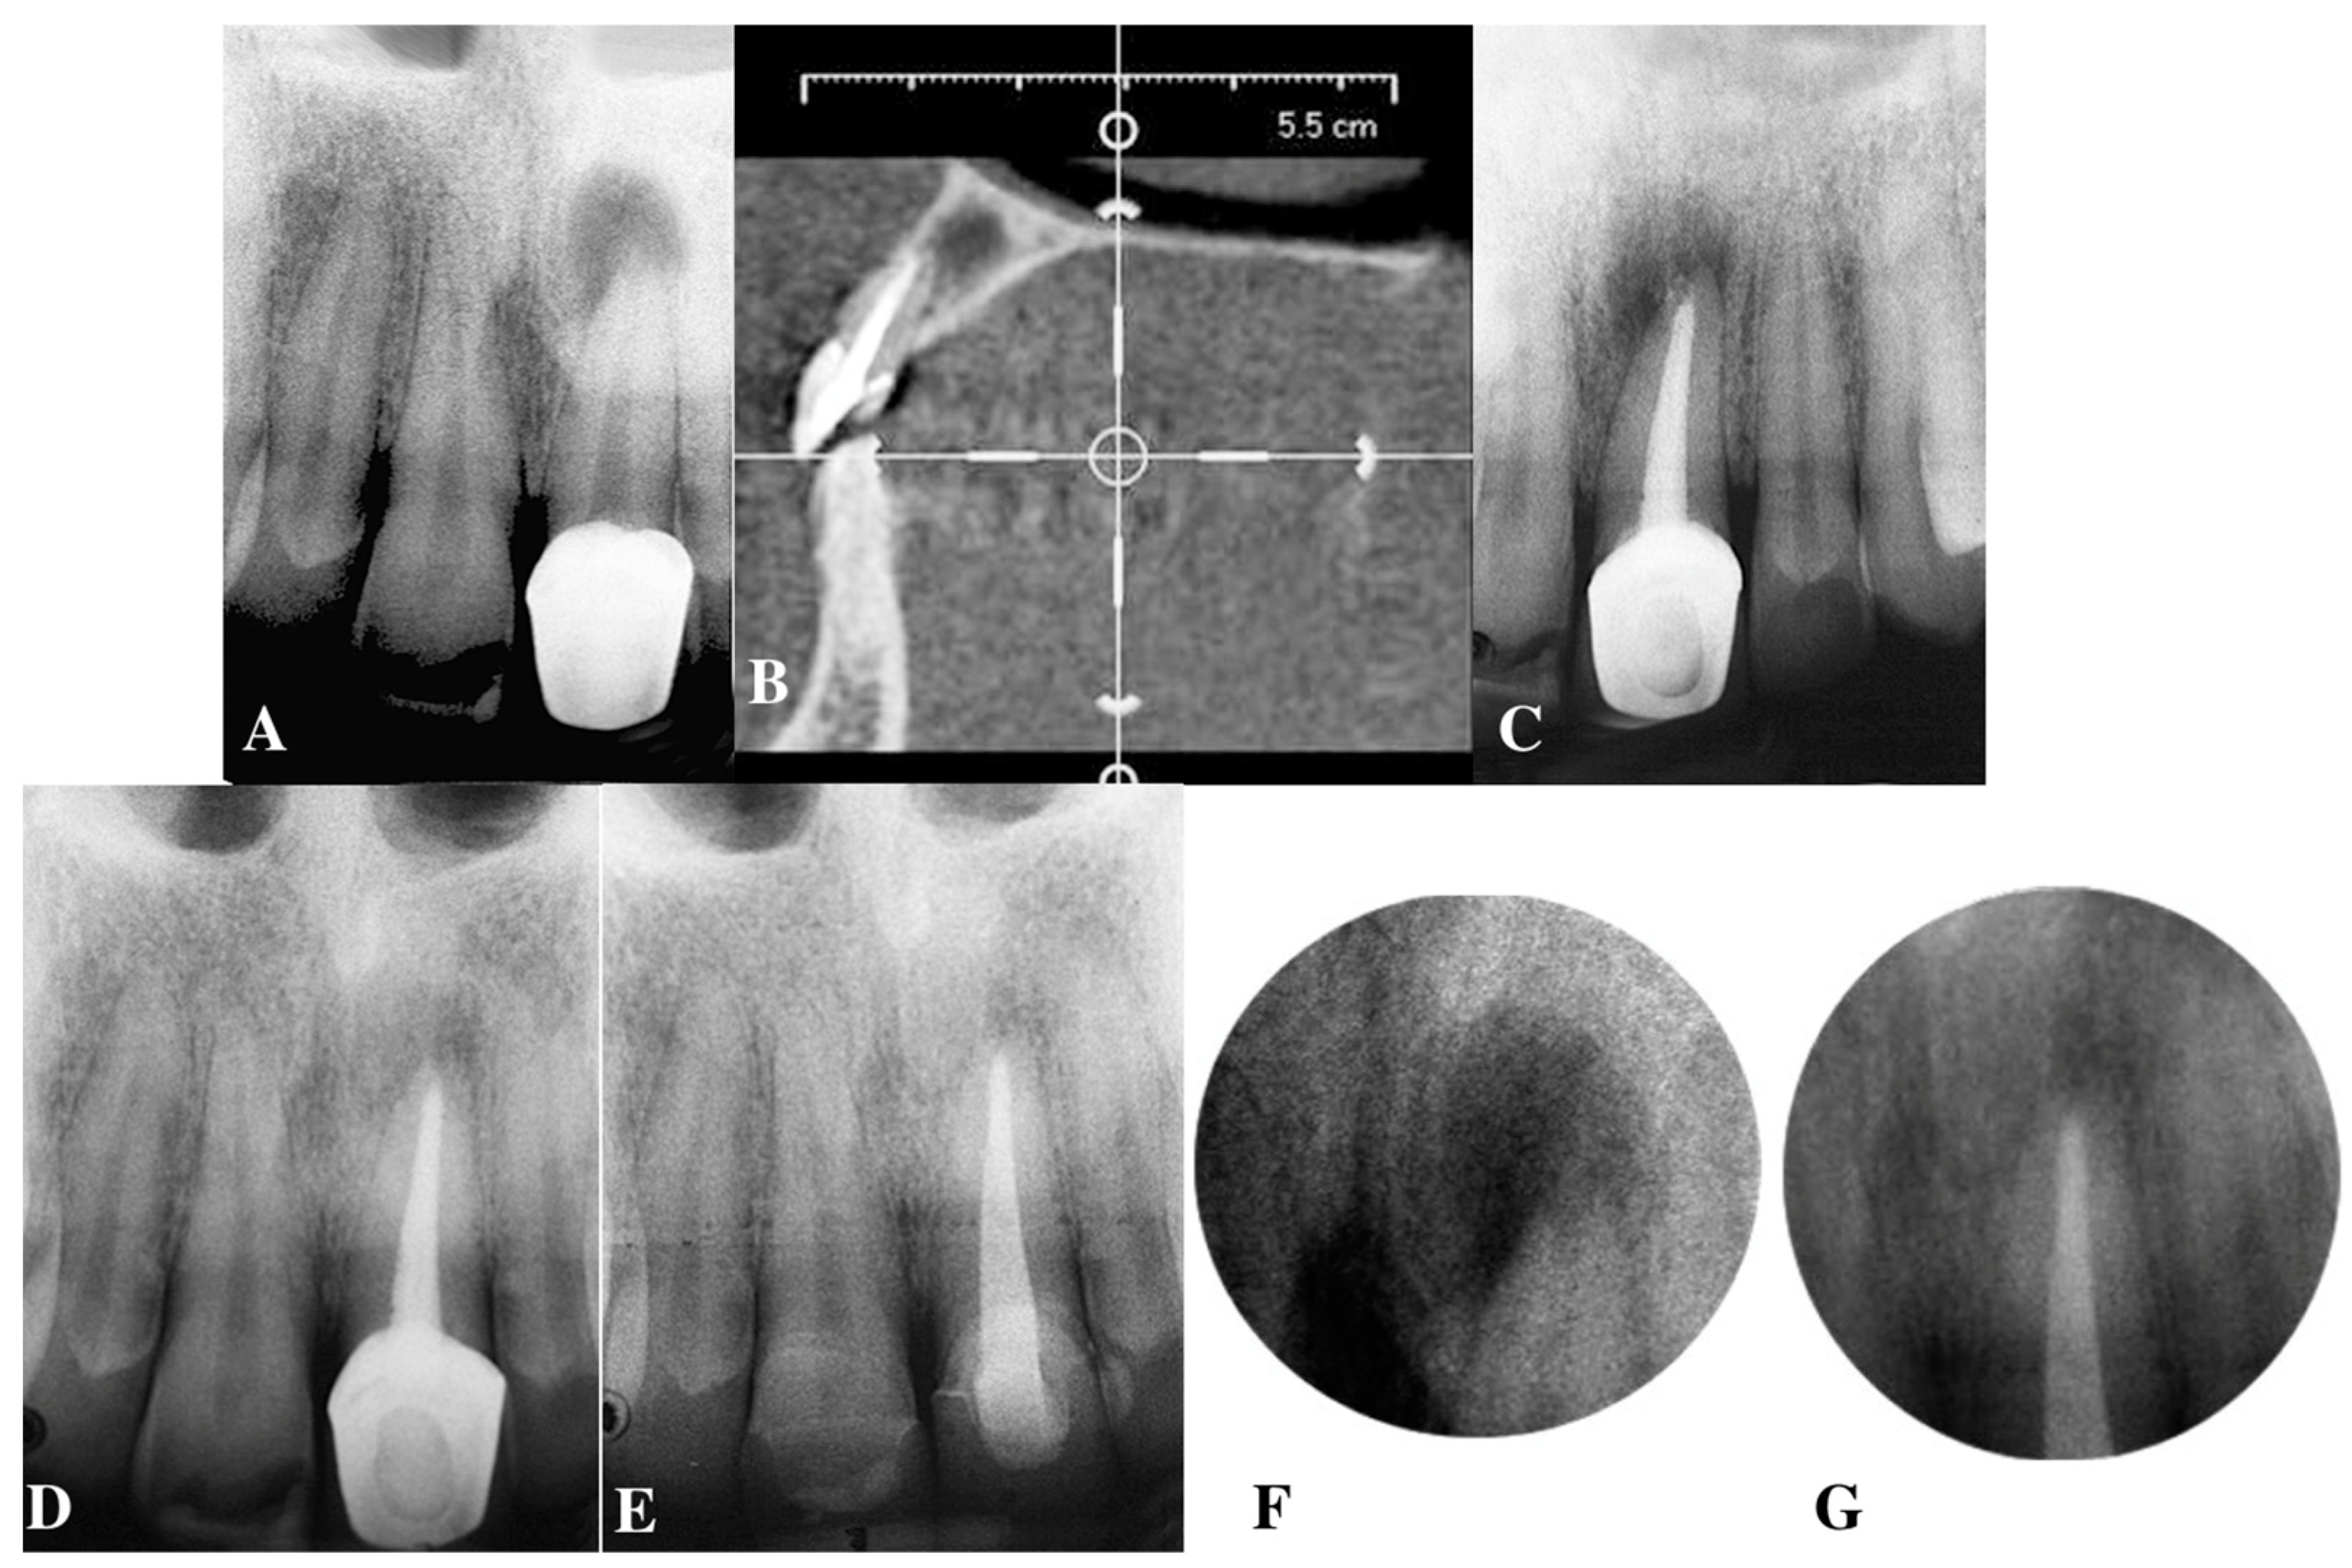

5.1. Apical Plug in Teeth with Apical Resorption and “Open Apex”

5.2. Apical Barrier